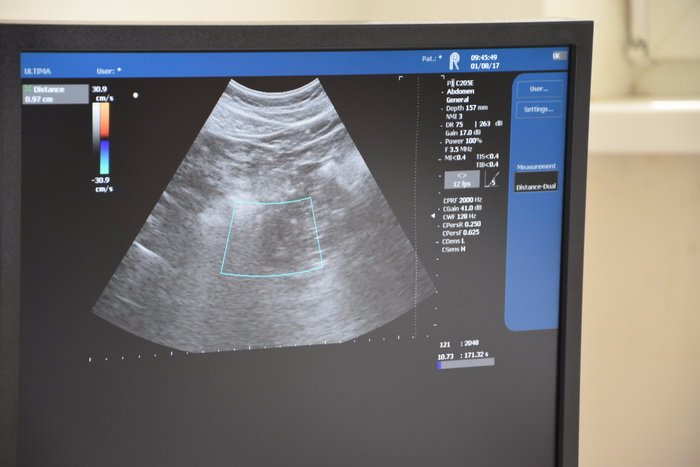

Відтепер у КЗ «Луцький центр первинної медико-санітарної допомоги» введено в експлуатацію новий ультразвуковий апарат.

Варто зазначити, що апарат українського виробництва. Закладом проведено тендер на придбання медобладнання. За результатом торгів переможцем було визначено харківську фірму «РАДМІР» з пропозицією закупівлі сучасного ультразвукового апарату ватрістю 950 тисяч гривень.

Перевагою даного апарату є наявність пристрою для еластографії – найсучаснішого методу для діагностування ступені жорсткості тканин, що дозволяє з більшою вірогідністю визначати чи злоякісне утворення, чи доброякісне (для щитовидної залози та для молочних залоз).

Апарат може бути використаний для проведення УЗ-досліджень органів черевної порожнини, нирок, сечостатевої системи, серця, поверхневих і периферичних судин, судин головного мозку, скелетно-м’язової системи та інших органів.